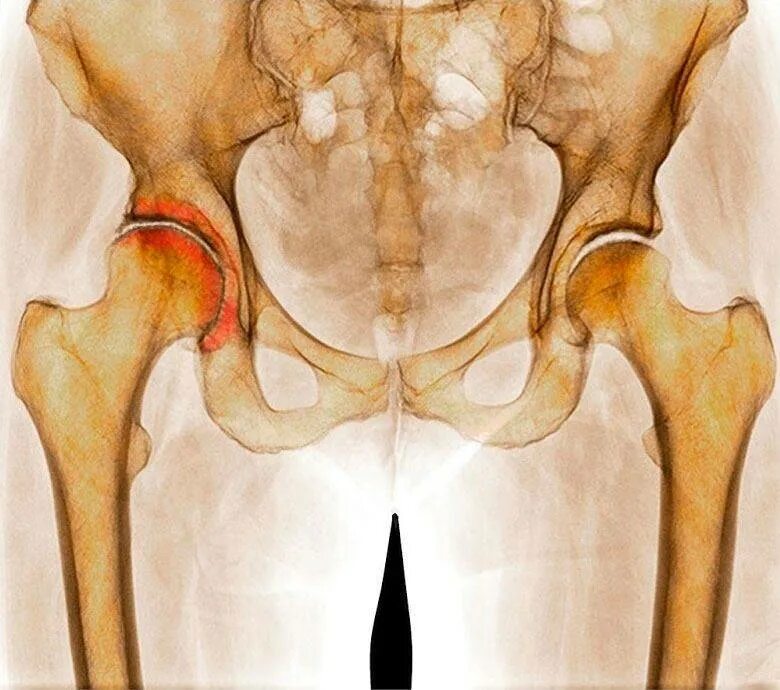

Тазобедренный сустав это